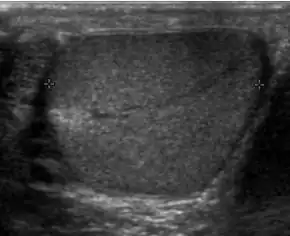

![]() Sonography of a normal testis. The normal testis presents as a structure having homogeneous, medium level, granular echotexture. The mediastinum testis appears as the

hyperechoic region located at the periphery of the testis as seen in this figure. | |

The normal adult testis is an ovoid structure measuring 3 cm in anterior-posterior dimension, 2–4 cm in width, and 3–5 cm in length. The weight of each testis normally ranges from 12.5 to 19 g. Both the sizes and weights of the testes normally decrease with age. At ultrasound, the normal testis has a homogeneous, medium-level, granular echotexture. The testicle is surrounded by a dense white fibrous capsule, the tunica albuginea, which is often not visualized in the absence of intrascrotal fluid. However, the tunica is often seen as an echogenic structure where it invaginates into the testis to form the mediastinum testis. In the testis, the seminiferous tubules converge to form the rete testes, which is located in the mediastinum testis. The rete testis connects to the epididymal head via the efferent ductules. The epididymis is located posterolateral to the testis and measures 6–7 cm in length. At sonography, the epididymis is normally iso- or slightly hyperechoic to the normal testis and its echo texture may be coarser. The head is the largest and most easily identified portion of the epididymis. It is located superolateral to the upper pole of the testicle and is often seen on paramedian views of the testis. The normal epididymal body and tail are smaller and more variable in position.